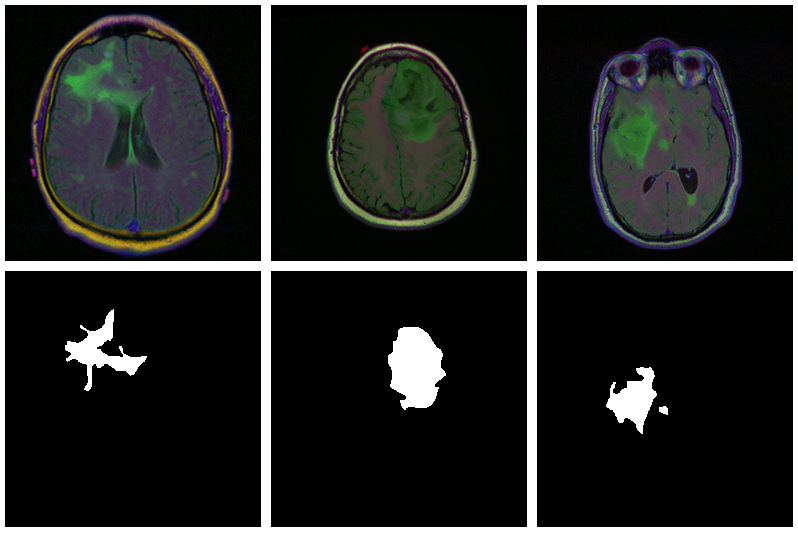

model$eval()Now, since we don’t have a separate test set, we already know the average out-of-sample metrics; but in the end, what we care about are the generated masks. Let’s view some, displaying ground truth and MRI scans for comparison.

par(mfcol = c(3, 8), mar = c(0, 1, 0, 1))

for (i in 1:8) {

img <- batch[[1]][i, .., drop = FALSE]

inferred_mask <- model(img$to(device = device))

true_mask <- batch[[2]][i, .., drop = FALSE]$to(device = device)

bce <- nnf_binary_cross_entropy(inferred_mask, true_mask)$to(device = "cpu") %>%

as.numeric()

dc <- calc_dice_loss(inferred_mask, true_mask)$to(device = "cpu") %>% as.numeric()

cat(sprintf("\nSample %d, bce: %3f, dice: %3f\n", i, bce, dc))

inferred_mask <- inferred_mask$to(device = "cpu") %>% as.array() %>% .[1, 1, , ]

inferred_mask <- ifelse(inferred_mask > 0.5, 1, 0)

img[1, 1, ,] %>% as.array() %>% as.raster() %>% plot()

true_mask$to(device = "cpu")[1, 1, ,] %>% as.array() %>% as.raster() %>% plot()

inferred_mask %>% as.raster() %>% plot()

}We also print the individual cross entropy and dice losses; relating those to the generated masks might yield useful information for model tuning.

While far from perfect, most of these masks aren’t that bad – a nice result given the small dataset!